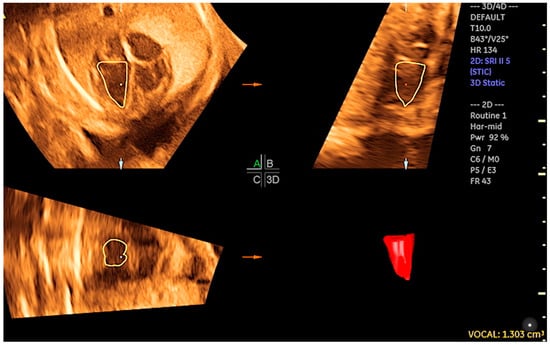

- Tedesco, G.D.; de Souza Bezerra, M.; Barros, F.S.; Martins, W.P.; Nardozza, L.M.; Carrilho, M.C.; Moron, A.F.; Carvalho, F.H.; Rolo, L.C.; Araujo Júnior, E. Reference Ranges of Fetal Cardiac Biometric Parameters Using Three-Dimensional Ultrasound with Spatiotemporal Image Correlation M Mode and Their Applicability in Congenital Heart Diseases. Pediatr. Cardiol. 2017, 38, 271–279. [Google Scholar] [CrossRef] [PubMed]